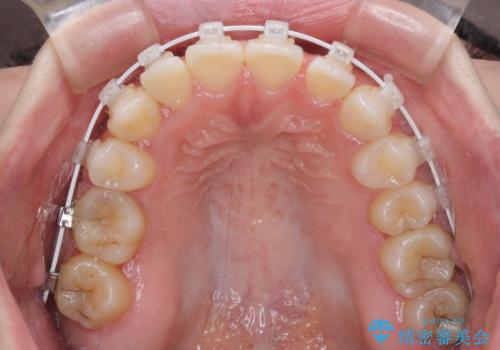

八重歯を改善 目立たないワイヤー装置での矯正治療

- 矯正装置

- 審美装置

- 八重歯を気にして来院された患者様です。

本来であれば八重歯の隣後方の歯を抜歯するのですが、その後ろの歯が乳歯であり後続永久歯もなかったため、乳歯を抜去することとしました。

前から5番目の乳歯は、後続永久歯である小臼歯と比べて幅径が大きいため、移動に時間がかかりましたが、きれいに仕上げることができました。